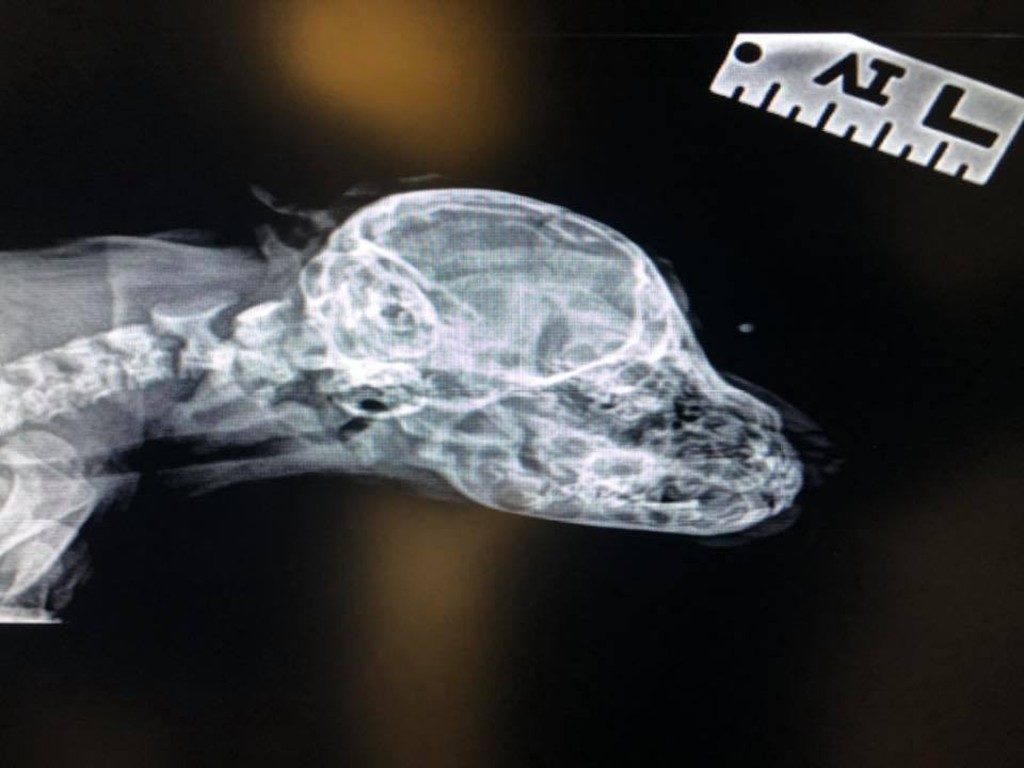

Narwhal had X-rays done on November 12 of this year and as far as the exam was concerned, there doesn’t seem to be anything medically wrong with him and the extra tail on his head. It serves no purpose except for making Narwhal the cutest rescue puppy in the world. As long as it stays a third of the size of his actual tail, there’s no real reason to cut it off.